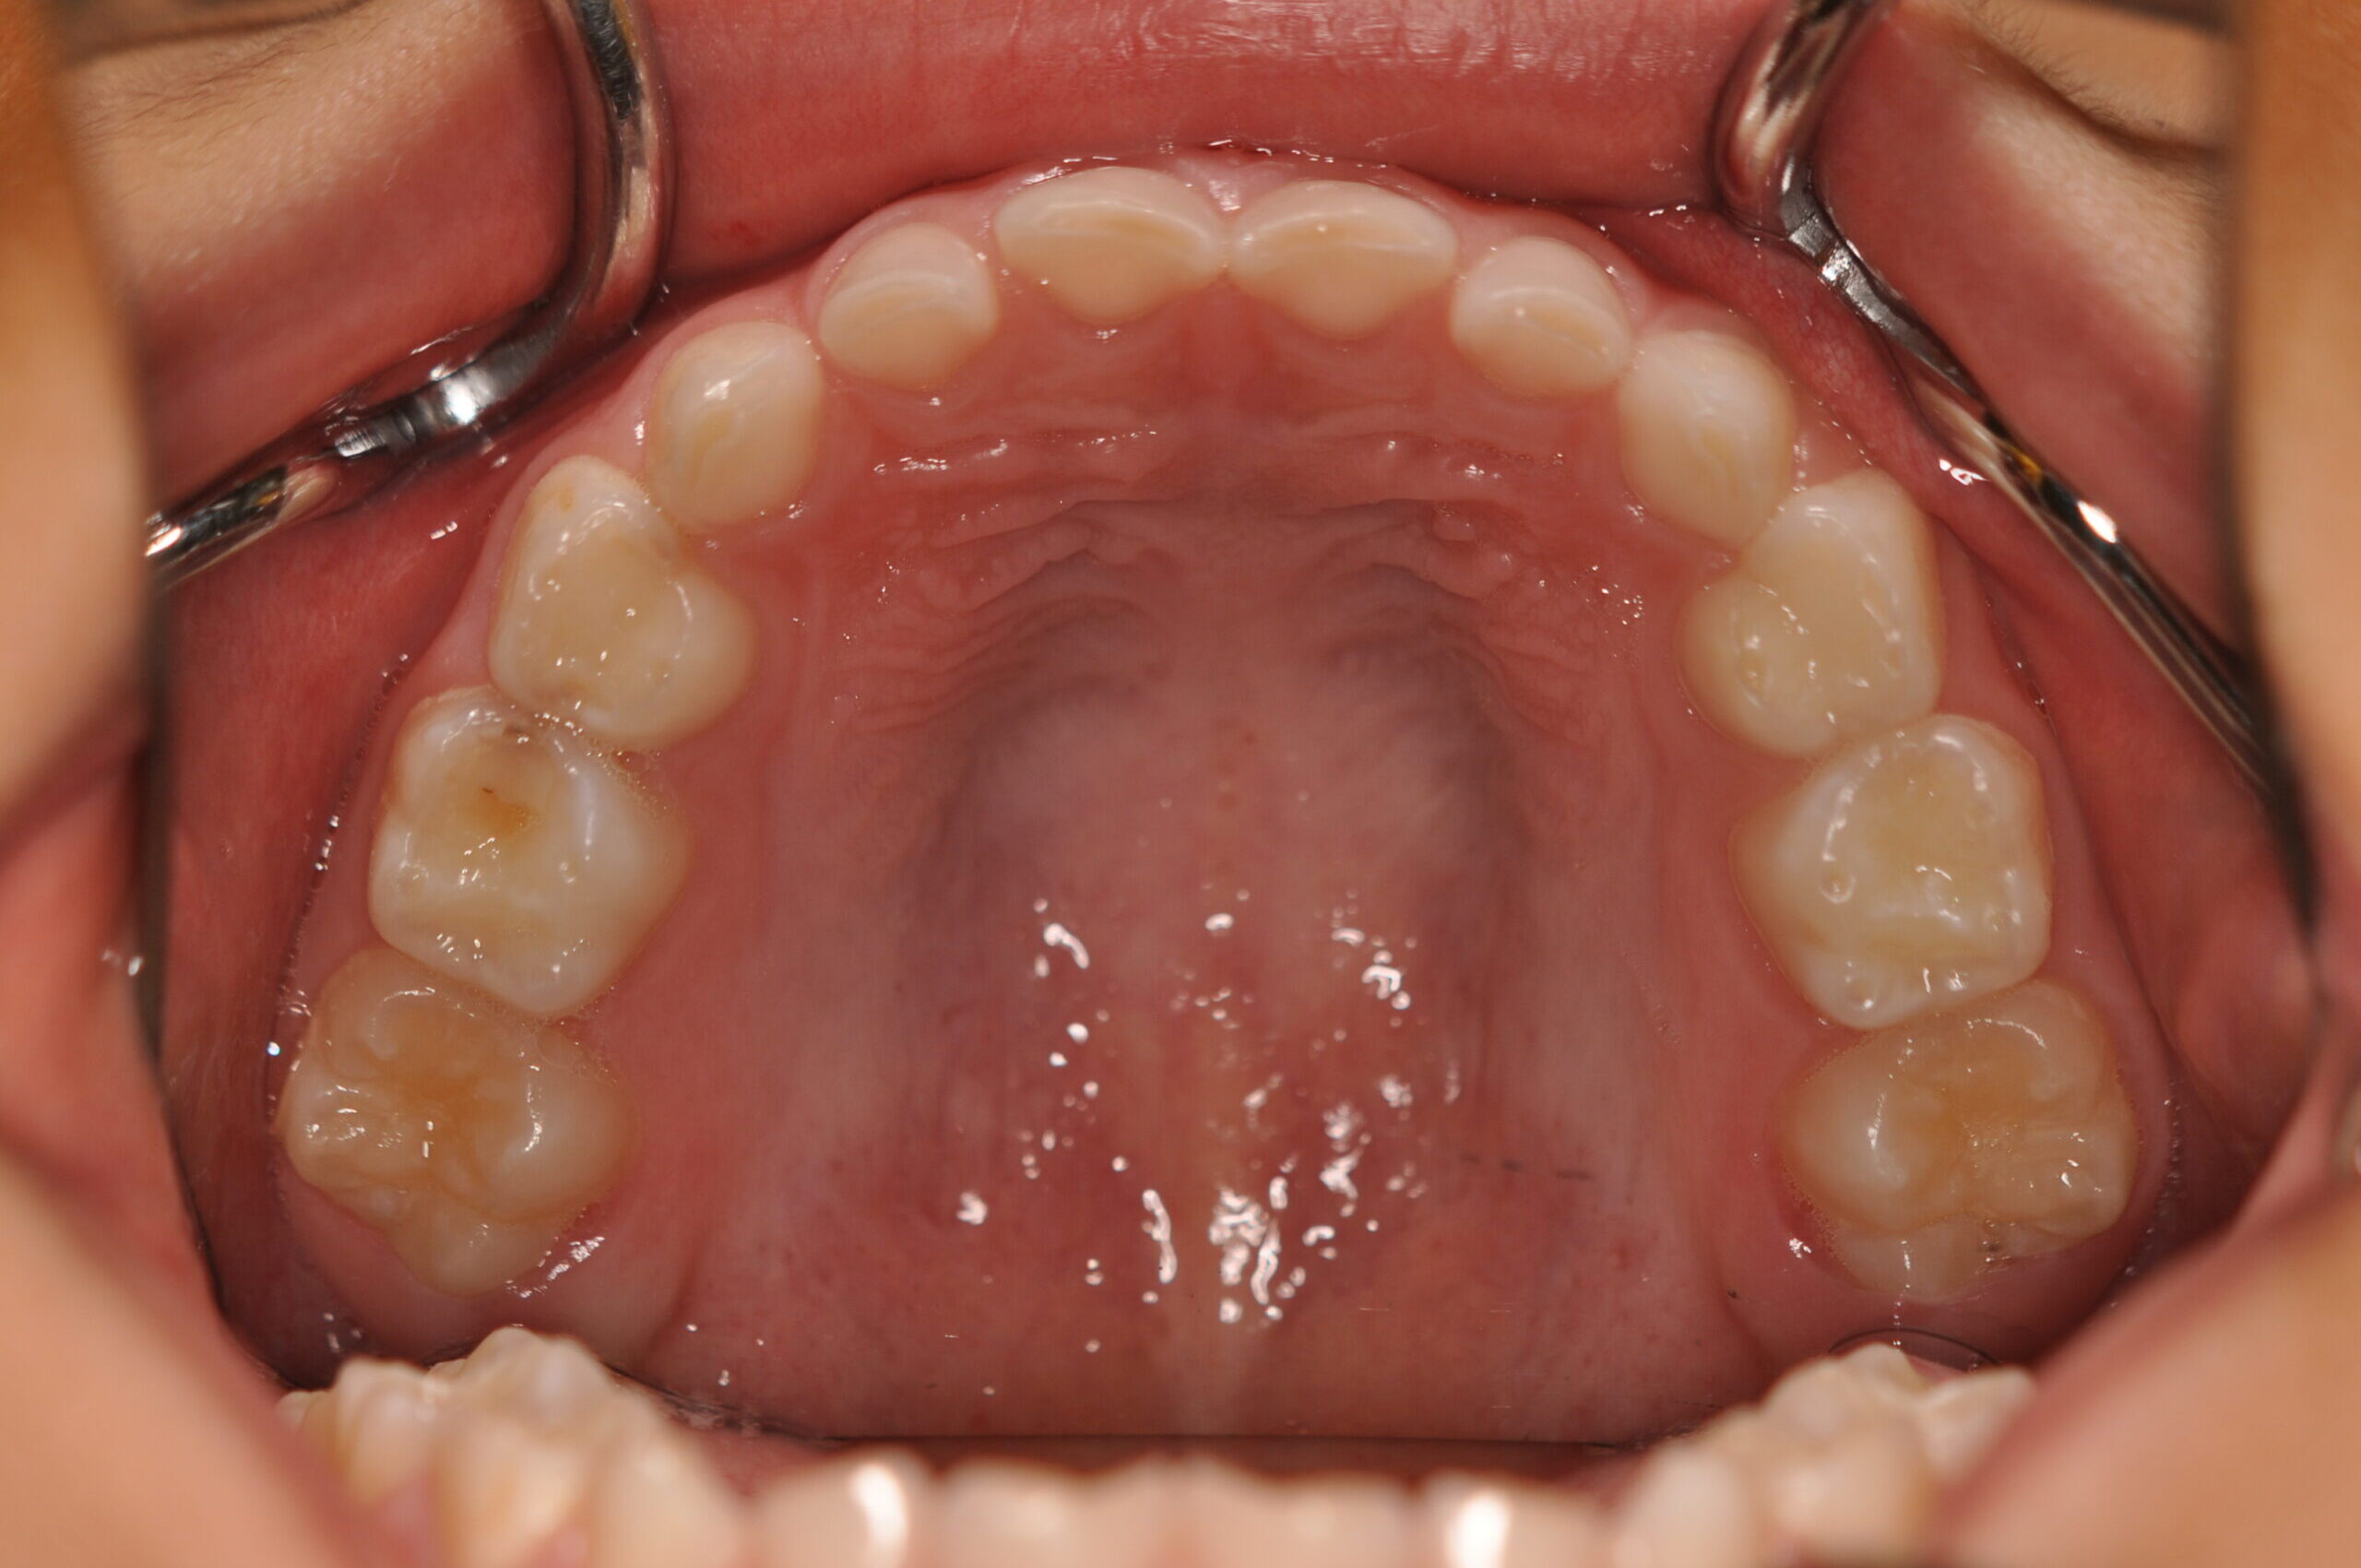

動的治療終了時

症例 症例 症例 症例

永久歯列に交換後、非抜歯の上、セルフライゲーションブラケット装置(デーモンシステム)で歯の配列と咬合関係の改善を行いました。